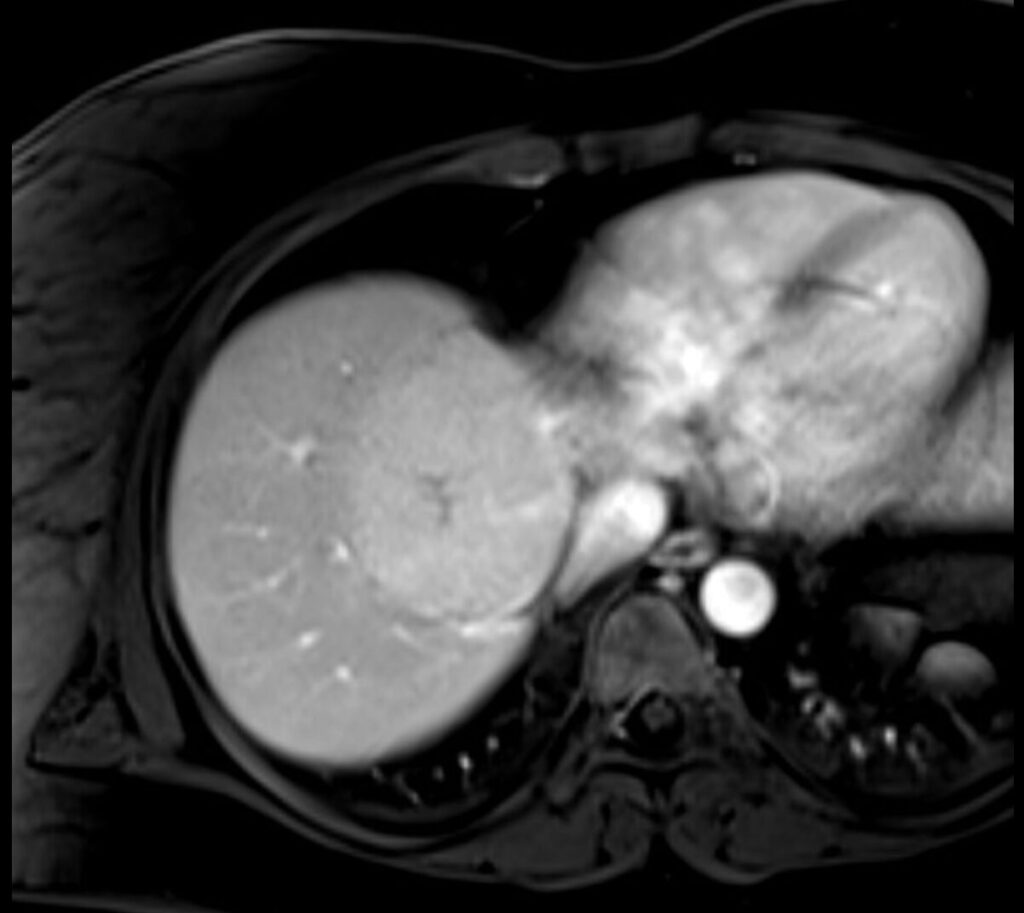

ADENOMA

- Tumore epatico benigno estrogeno-dipendente.

- Può andare incontro a degenerazione maligna (10% se >10 cm) e a rottura con emorragia intraperitoneale per cui è indicata l’asportazione chirurgica se > 5 cm.

- Singolo o multiplo.

Aspetto RM

- Alterazione focale caratterizzata da segnale intermedio in T2, isointensità in T1, con abbattimento del segnale nelle sequenze in opposizione di fase per la presenza di grasso intralesionale.

- Allo studio dinamico si caratterizza per precoce enhancement arterioso con isointensità tardiva.

- In fase epatospecifica è ipointenso rispetto al parenchima circostante per l’assenza di un sistema duttale biliare

- Esistono differenti sottotipi di adenoma caratterizzati da un diverso rischio di trasformazione maligna

- Infiammatorio (I-HCA): è il sottotipo più frequente (40-55%).

Prevalente nelle donne, è spesso associato a obesità, steatosi epatica e sindrome metabolica.

Caratterstica RM: segno dell’atollo in T2 – rim periferico iperintenso con porzione centrale isointensa. - HNF-1𝛂 mutato (HNF-1𝛂 HCA): pressoché esclusivo del sesso femminile. Per via dell’attivazione di vie lipogeniche è caratterizzato dalla presenza di grasso intralesionale. Molto rara la trasformazione maligna. Caratterstica RM: abbattimento del segnale nelle sequenze T1 out-of-phase.

- Con mutazione della β-catenina (β-HCA): più frequente nel sesso maschile. Alto rischio di trasformazione maligna (6%). Caratterstica RM: segnale eterogeneo in T1 e T2, talvolta con scar centrale.+